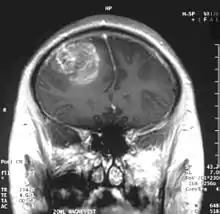

Kumaravel Somasundaram (born 8 October 1962) is an Indian cancer biologist and a professor at the Department of Microbiology and Cell Biology of the Indian Institute of Science. Known for his studies on the therapeutics of Glioblastoma, Somasunderam is an elected fellow of all the three major Indian science academies namely, the National Academy of Sciences, India, the Indian Academy of Sciences and the Indian National Science Academy. The Department of Biotechnology of the Government of India awarded him the National Bioscience Award for Career Development, one of the highest Indian science awards, for his contributions to biosciences in 2006.

Somasundaram's work is centered around the studies of oncoviruses, tumor suppressor genes, gliomas and microRNAs and he has done advanced research on glioblastoma, an aggressive form of cancer affecting the brain.[8][9] The group led by him is engaged in work concerning the determination of the role of cellular tumor antigen p53 in glioma, regulating the protein, p73 in cervical cancer patients, using Adenovirus early region 1A, a tumor suppressor gene, the analytical study of BRCA1 gene in breast cancer and the analysis and regulation of SV2A, a synaptic vesicle protein.[3] He demonstrated that glioblastoma spreads rapidly by producing macrophage colony-stimulating factor (MCSF) in large quantities which in turn stimulate the growth of blood vessels in the tumor.[10] He proposed that the MCSF interacted with the anti-tumor microglial cells of the human body and induced them to produce Insulin-like growth factor-binding protein 1 (IGFBP1), thereby impairing the capacity of microglial cells to fight the tumor cells, a process he called befriending. The discovery of this new molecule, IGFBP1 and its role in glioma angiogenesis, led to a collaborative investigation which involved four research institutions namely National Institute of Mental Health and Neuro Sciences, Sri Sathya Sai Institute of Higher Medical Sciences and Institute for Functional Genomics (INSERM) of the University of Montpellier, apart from the IISc.[11] The research team led by Somasundaram and Phillipe Marin of INSERM validated the earlier findings and proposed a new therapeutic protocol for glioblastoma which targeted IGFBP1, rather than Vascular endothelial growth factor (VEGF) which earlier treatment methods attacked.[12] The researchers, later, released their findings through a paper, Glioblastoma-derived Macrophage Colony Stimulating Factor (MCSF) Induces Microglial Release of Insulin-like Growth Factor-Binding Protein 1 (IGFBP1) to Promote Angiogenesis, published in the Journal of Biological Chemistry.[13] Work is in progress at his laboratory for developing biomarkers (twenty genes of which is named gene X, have already been discovered)[14] for which detailed study is being conducted on microRNA, DNA methylation, modifications of chromatin and gene fusions.[4][15] His studies have been documented by way of a number of articles[16][17][note 1] and ResearchGate, an online repository of scientific articles has listed 178 of them.[18] He has also conducted workshops[19][20][21] including the Workshop on Next Generation Sequencing organized by the Council of Scientific and Industrial Research in November 2013[22] and has delivered invited or plenary speeches at various conferences and seminars[23] and the 5th annual meeting of the Proteomics Society, India held in September 2013 was one among them.[24]